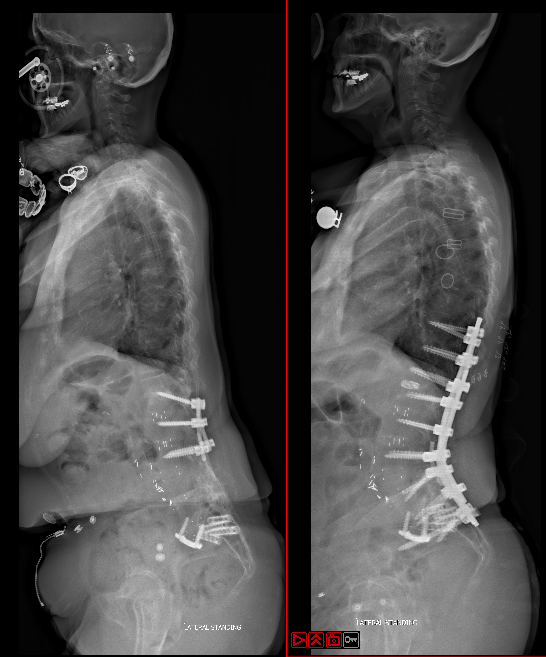

Deformity Surgery